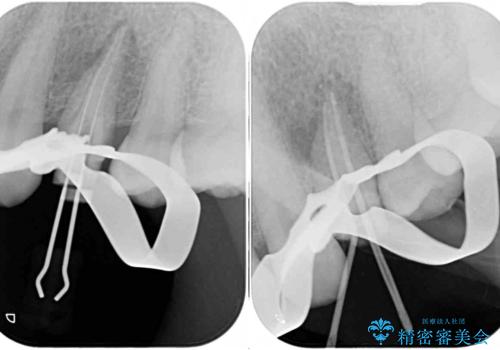

診査の結果、既に歯の神経は失活しており、レントゲンより根尖部に病変を認めました。

根管治療を行った後にオールセラミッククラウンにて補綴することとしました。

補綴後6ヶ月経過しレントゲンを撮影したところ、根尖周辺の病変が消失していることが確認できました。